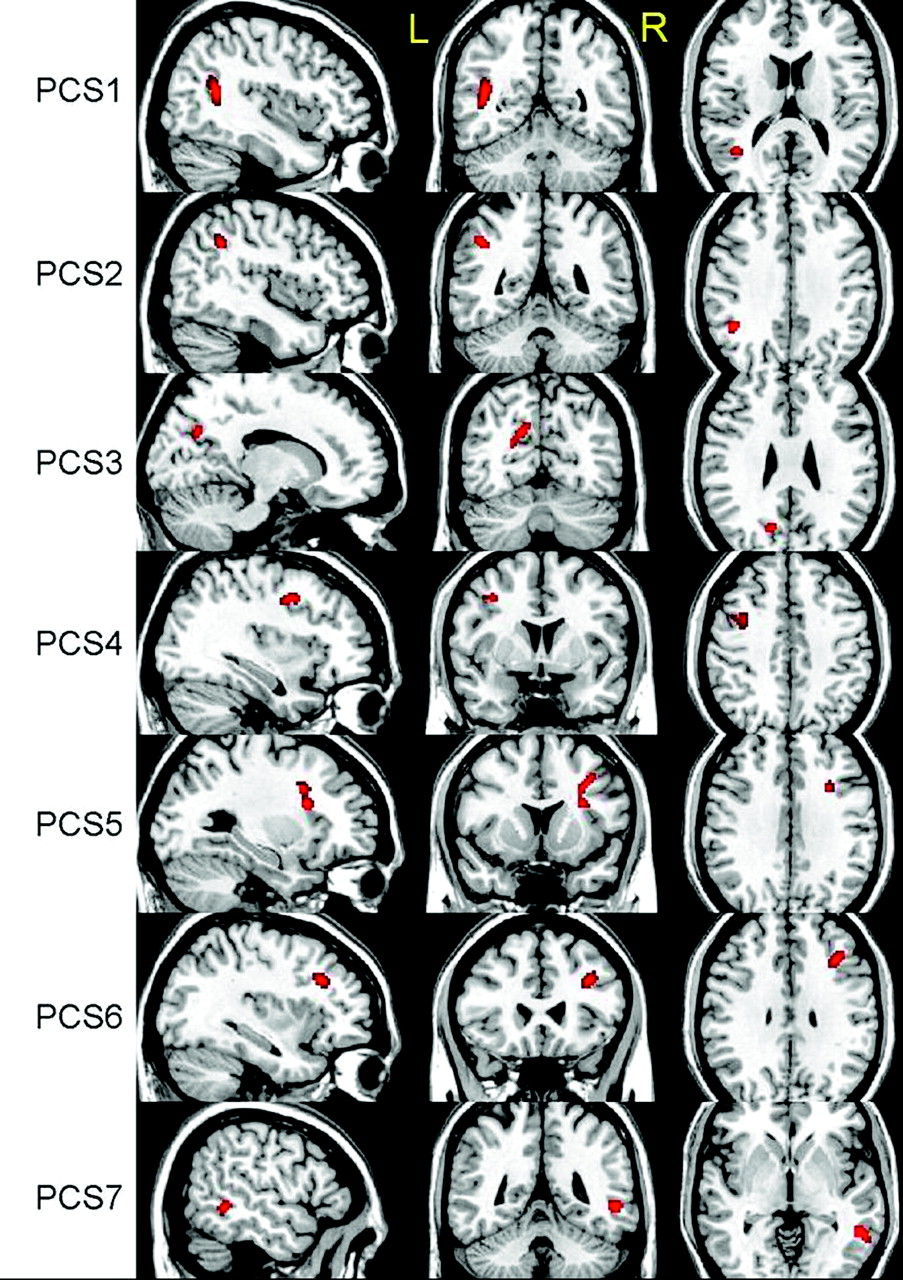

VBA revealed 6 regions with significant decreases in ADC, t(18) = 3.6, P < .001, by using a cluster size of >50 voxels (Fig 1). As expected, most regions identified were located in WM structures with the exception of the left thalamus. No region was found to have a significant increase in ADC by using the same thresholds. The linear regression analysis between ADC and RPCSQ indicated a significant negative relation in 7 regions, t(18) = 3.3, P < .002, by using a cluster size of >40 voxels (Fig 2), which were again located predominantly in the WM. Again, no significant regions between ADC increase and RPCSQ were identified, consistent with the results of the group analysis.

Three-plane views of 7 regions (PCS 1–7) identified by ADC-RPCSQ analysis, superimposed on a structural image.

Linear regression analysis of the relation between ADC and BSI revealed 7 regions that were negatively related by using the thresholds above. No positive relations were found (Fig 3). Twenty regions of significant difference were identified by VBA, (ie, 6 regions identified by group analysis of ADC only; 7, by analysis of ADC-RPCSQ; and 7, by analysis of ADC-BSI). Additionally, 3 composite regions were created on the basis of the results of these 3 analyses. Therefore, there were a total of 23 regions for the following region-based analyses.

The relation of DTI parameters including additional analyses examining the relation between ADC and RPCSQ and between ADC and BSI demonstrated several regions with significant decreases in ADC in patients with mTBI. Not unexpectedly, ADC was related to the BSI in regions identified by ADC-RPCSQ analysis, and ADC was also correlated with RPCSQ in regions identified by ADC-BSI, owing to the high correlation between RPCSQ and BSI (r = 0.62). All of this suggests that perturbation of WM and its interconnectivity resulting from the neuropathologic effects of mTBI may be associated with PCS symptoms. It may be that early identification of pathologic brain changes in mTBI will aid in the identification and classification of the disorder, which is likely underdiagnosed due to lack of specific medical biomarkers to date37 and in turn may lead to earlier and more effective interventions.38,39